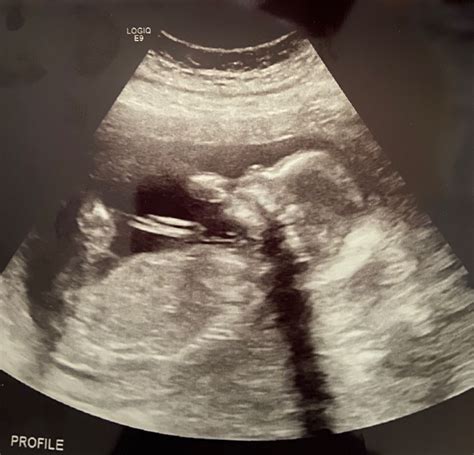

This image highlights the baby's position and movement, which are important indicators of overall health and development.

This image highlights the baby's position and movement, which are important indicators of overall health and development. The 20 week ultrasound helps ensure that the baby is progressing smoothly and that any potential issues are identified early.